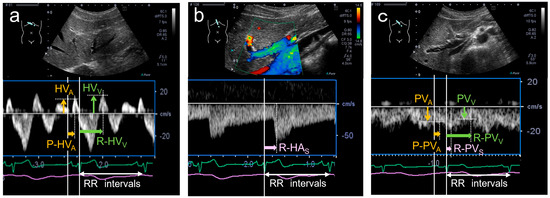

Portal venous (PV) flow Doppler velocimetry assesses venous congestion in heart failure, showing PV pulsatility due to backward transmission of right atrial pressure (RAP) through the sinusoids. However, PV pulsatility has also been observed under physiological conditions. We aimed to elucidate the mechanisms and contributing factors of PV pulsatility in healthy adults. Pulsed-wave Doppler recordings of the hepatic venous (HV) and PV flow were obtained with electrocardiography. A- and V-wave velocities and their timings relative to the P- and R-waves (P-HVA, R-HVV) were measured from the HV waveforms. From PV waveforms, atrial and ventricular systolic descent flow velocities and their timings (P-PVA, R-PVV) were measured. The PV pulsatility index (VPI) was calculated. There were no differences between P-PVA and P-HVA, and between R-PVV and R-HVV, indicating similar waveforms. Seventy-nine percent of participants showed a VPI ≥ 0.3, with a higher VPI in younger vs. older participants (0.7 vs. 0.3, p < 0.01). Only age was independently associated with VPI (β = −0.56, p < 0.01). PV pulsatility was common in healthy adults, suggesting RAP transmission via the sinusoids; this physiological phenomenon was attenuated with aging. These findings highlight the importance of considering age-related physiological changes when interpreting the PV flow. Full article